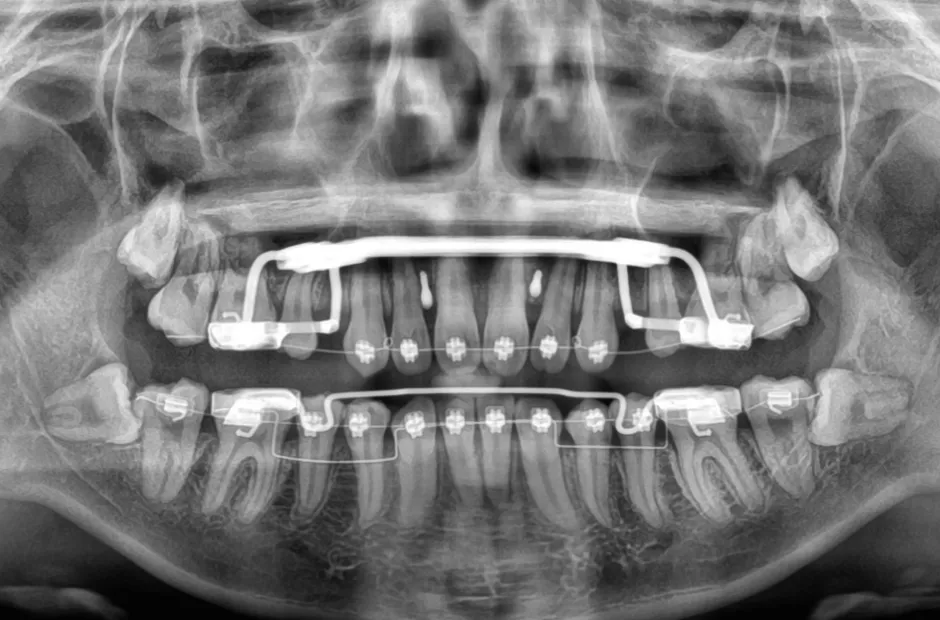

治療中